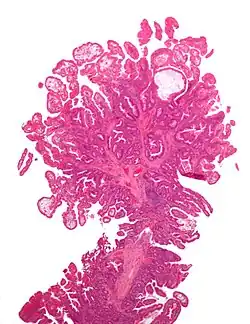

Gallery

-

Microvesicular hyperplastic polyp. H&E stain. -